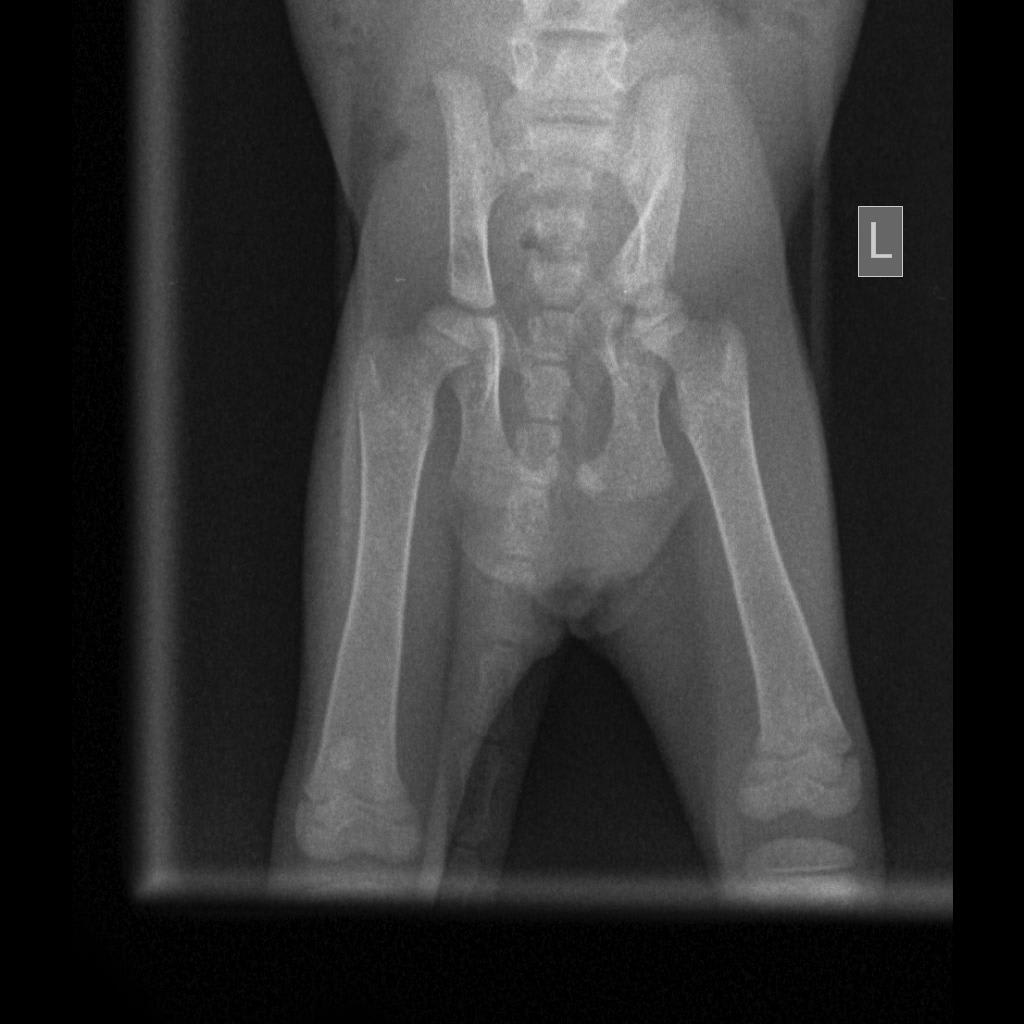

On 13th 2am-3am i hear my kitten screaming from my front gate and and saw her flopping on the ground in pain. I rushed to pick her up and laided her on my lap making her calmed. I stayed awake all night because my kitten will immediately start flopping in pain again. Has brought her to the vet in the evening and the did an xray scan. The vet told me that my kitten left pelvis bone is fractured. But her is limping on her back right leg. The vet said the is nothing much can do to a kitten

In your x-ray I do see the broken pelvis and it looks like it is left sided based on the markers on the x-ray. I'm surprised that she would be putting weight on her left leg, but it's possible that she has another injury that wouldn't be apparent on the x-ray or that the x-ray was mislabeled if this is the case. I would recommend calling or rechecking with the vet - they might want to repeat an x-ray to see if things have changed and if there is something wrong on the other side of her pelvis and leg.